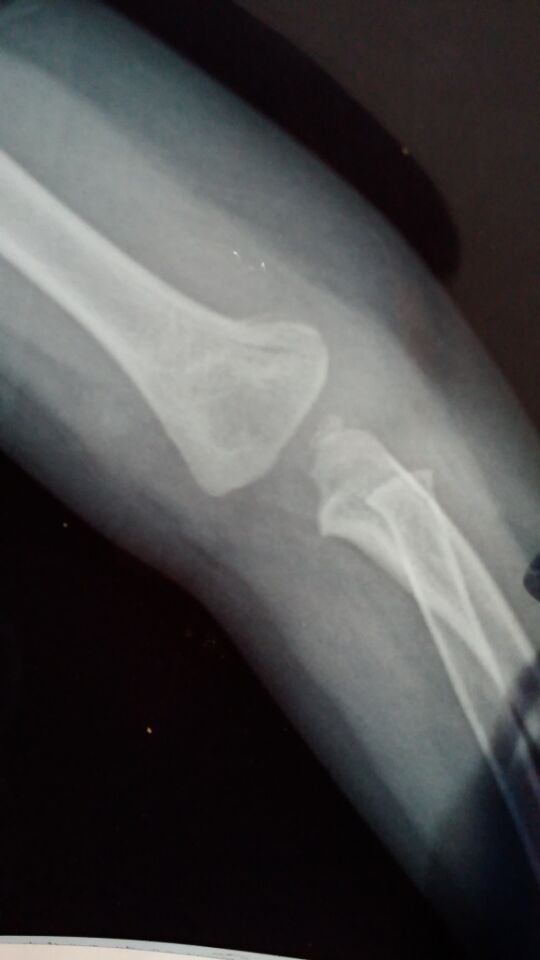

没打石膏是刚摔到拍的 打石膏是今天复查的 请问恢复得好吗?需要打多久石膏?宝宝一岁半 点击展开 匿名用户 2015-07-19 22:49 为您推荐: 其他回答 你好,根据你所描述的情况及提供的片子来看,尺桡骨脱位,行复位后外固定即可。石膏固定1个月左右。 sΰ 2015-07-19 23:23 相关问题 四个月宝宝,半个月复查,医生说再过6天恢复可以就能去石膏了 孩子左肱骨髁上骨折一周后的复查片子,麻烦医生帮我看看恢复的怎么样呢?还有医生为什么把石膏割了一个大 八岁孩子今天上体育课,被其他孩子推了以后,到医院检查,右肱骨髁上骨折,打完石膏回到家,现在不知道要